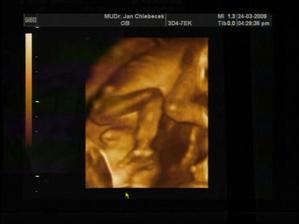

13tt - NT screening dopadl na jedničku, nemůžeme se dočkat další kontroly

15+6tt - čekáme kluky!!! V bříšku už se pěkně melou, takže musíme na kontrolu do nemocnice, čípek naštěstí v pořádku (36mm)

19+3tt - tripple testy dopadly na 1*, čípek také v pořádku, děloha klidnější a ztratil se nám jeden pindík!! Uvidíme za pár dní, jestli ho pan doktor zase najde

19+6tt - pindíci jsou dva a kluci se mají čile k světu, pěkně se v bříšku pošťuchujou

20+6tt - kluci se mají čile k světu, váhy A-323g + B-354g, velký ultrazvuk dopadl výborně